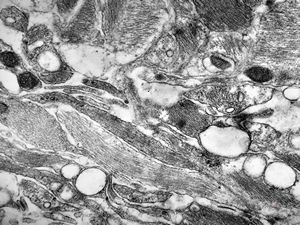

F,49y. | purulent meningitis- meningococcal v.s.

F,49y. | purulent meningitis- meningococcal v.s.

F,49y. | purulent meningitis- meningococcal v.s.